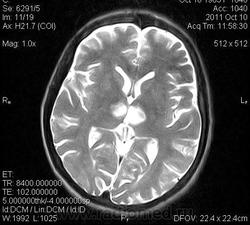

женщина 1963 года рождения. давность заболевания 10 дней.

ОНМК в бассейне правой и левой СМА (центральные ветви), подострый период.. Билатеральность нарушений может быть обусловлена вариантом строения Виллизиева круга.

Билатеральный таламический инфаркт. Либо венозный, либо вследствие закупорки одной из ветвей задней мозговой артерии - ЗМА (вариан развития ЗМА). Но не средней мозговой артерии (СМА). Мне представляеться, что здесь второе... За венозный инфаркт данных не вижу.